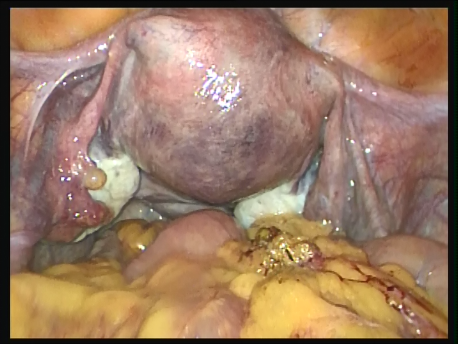

Endoscopy involves placing a small telescope into the human body through tiny incisions (3-5mm). The telescope can be placed into the abdomen via small tubes called ports (laparoscopy) or inside the uterus through the mouth of the uterus or cervix (hysteroscopy).

Various fine and delicate instruments are available through which complicated surgeries can be performed inside the abdomen or the uterus. In fact, endoscopic surgery has become the gold standard of surgery today. Since most of these instruments are being manufactured locally, the cost of endoscopy has also reduced significantly since its advent in the eighties.